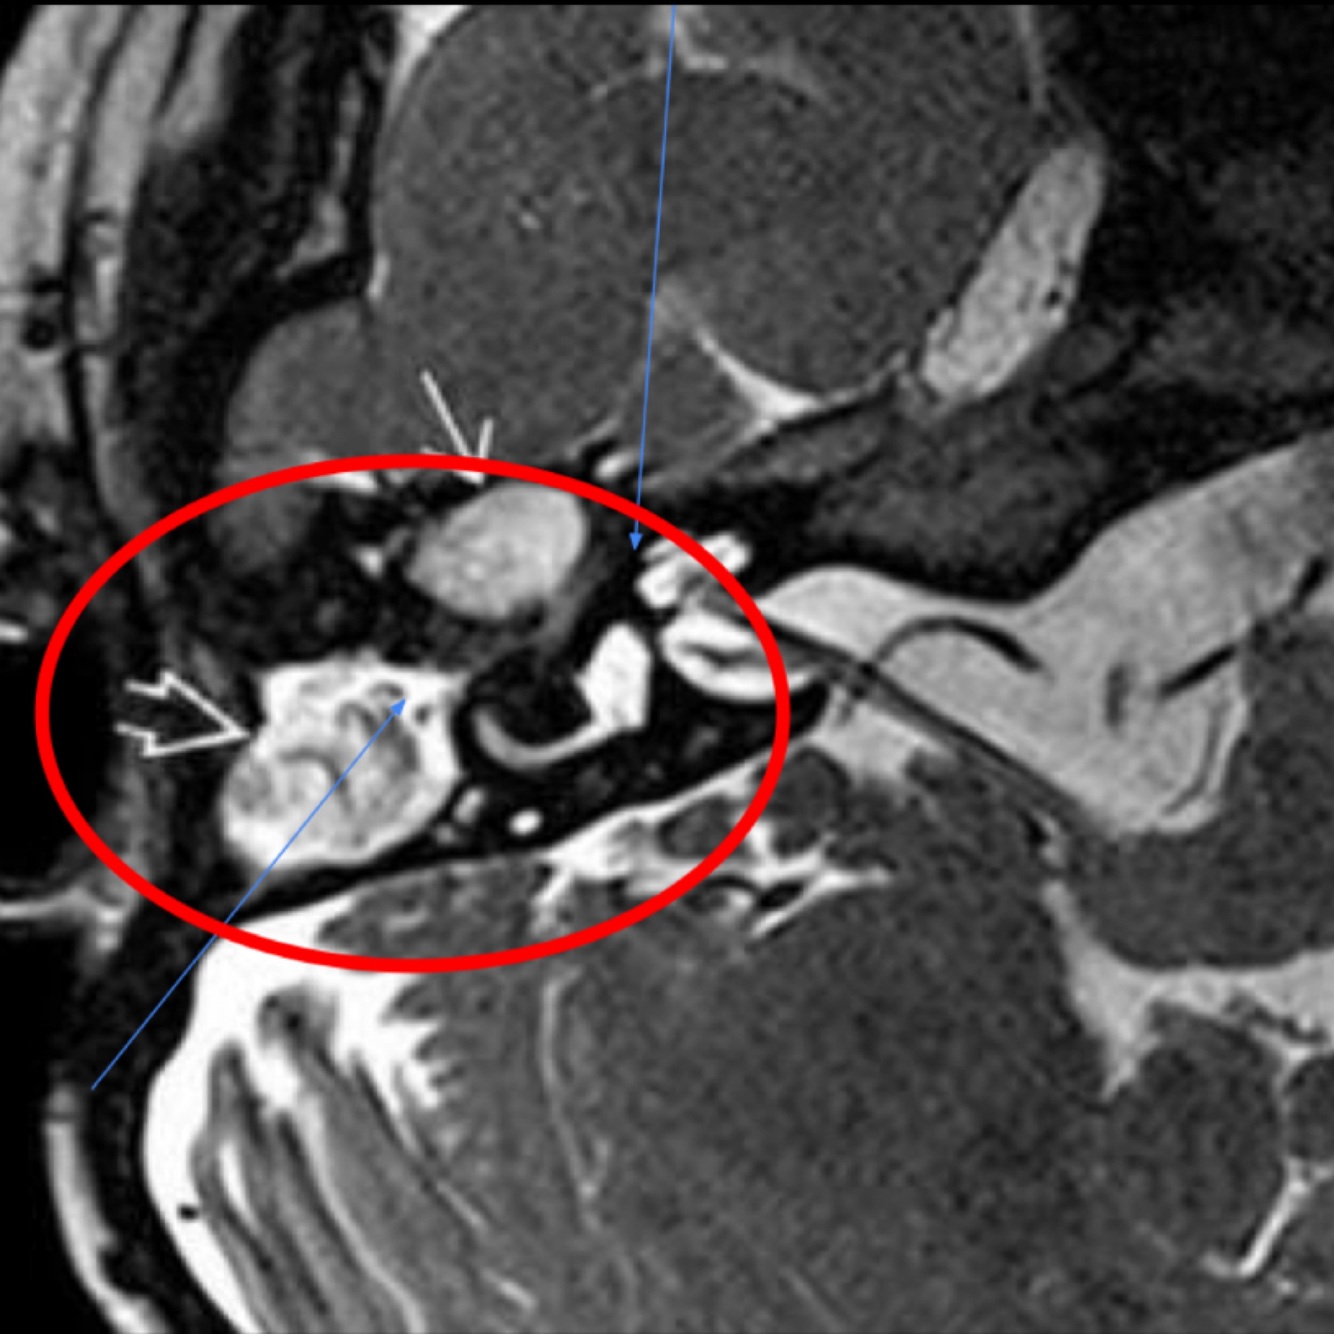

Q

De que enfermedad se trata y qué complicacion está presentando

A

Mastoiditis con invasión a SNC con un absceso que provoca una meningitis

Para que sirve la RM en mastoiditis y específicamente en T2

• Hiperseña

• Captación de contraste